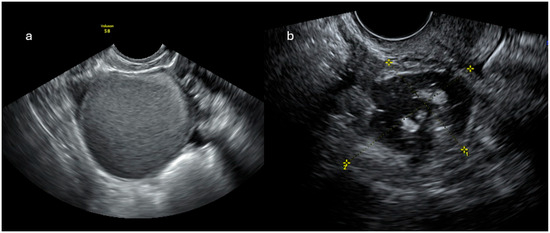

Background/Objectives: Extramedullary involvement in multiple myeloma represents an aggressive disease phenotype, associated with reduced survival and an unfavorable prognosis. Thoracic manifestations are rare and remain poorly characterized in the literature. Methods: We conducted a retrospective, single-center study at the Fundeni Clinical

Background/Objectives: Extramedullary involvement in multiple myeloma represents an aggressive disease phenotype, associated with reduced survival and an unfavorable prognosis. Thoracic manifestations are rare and remain poorly characterized in the literature. Methods: We conducted a retrospective, single-center study at the Fundeni Clinical Institute, including patients diagnosed with multiple myeloma between February 2010 and February 2025. The study cohort consisted of 34 patients with infiltration of the pulmonary parenchyma, pleura, or the presence of myelomatous pleural effusion. Diagnosis was confirmed using a combination of imaging modalities (computed tomography or magnetic resonance imaging), cytological examination, immunophenotyping, and histopathological confirmation whenever feasible. Results: Out of a total of 2012 patients with multiple myeloma, the incidence of pleuro-pulmonary extramedullary involvement was 1.6%. The median age at diagnosis was 58 years. Pleuro-pulmonary disease was present at initial diagnosis in 26.5% of cases, while 73.5% developed it at relapse. The most common presentation involved combined pleural involvement and myelomatous effusion (70.6%). Adverse prognostic markers included elevated β2-microglobulin levels (in over 80% of cases) and increased lactate dehydrogenase (LDH) in approximately 50%. Cytogenetic abnormalities such as del(17p), t(4;14), t(14;16), t(11;14), and 1q gain were identified. The median overall survival (OS) from the diagnosis of pleuro-pulmonary extramedullary disease was 16 months, with a 2-year survival rate of 25%. No patient survived beyond 5 years. The median progression-free survival (PFS) was 9 months. Conclusions: Our findings confirm the aggressive clinical course and poor prognosis of these disease manifestations, mainly when they occur at relapse. In the absence of standardized treatment guidelines, individualizing therapy and accessing novel strategies may be essential for improving patient survival.